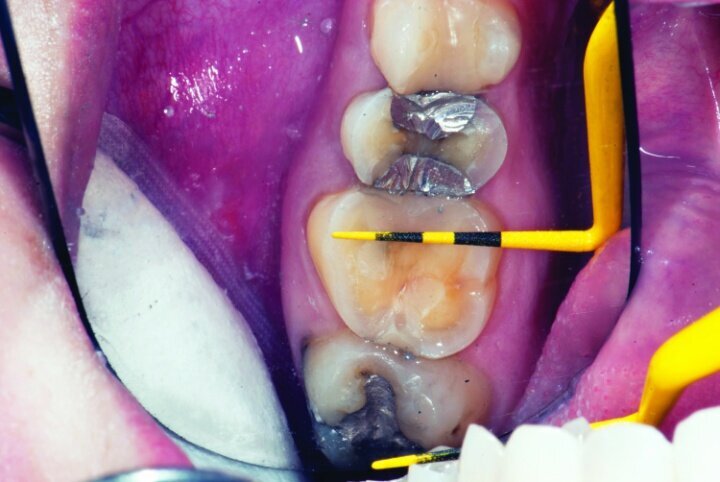

This patient presented for restorations of teeth #3 and #4 (Fig. 1a). Because of the size of the existing restorations, these teeth were diagnosed as structurally compromised (Figs. 1b, c). The prognosis without treatment was fair.

Depth guide cuts were made using a 330 bur, which has a 2 mm cutting surface (Figs. 2a–3b). This ensures 2 mm of occlusal reduction to accommodate 2 mm of material thickness on the occlusal surface of the restoration.

Gross occlusal reduction was completed using a KS7 bur to the depth cuts (Figs. 4–8b, 9c). Adequate clearance was verified with a 2 mm prep check from Common Sense Dental Products.

After gross occlusal reduction was completed, the remaining enamel ring was measured (Figs. 9a, b). The enamel rings were noted to be 1.5 mm, and the teeth were prepared for adhesively retained restorations. If the enamel rings were less than 1 mm, the teeth would have been prepared on the axial walls to create retention for cohesively retained crowns.